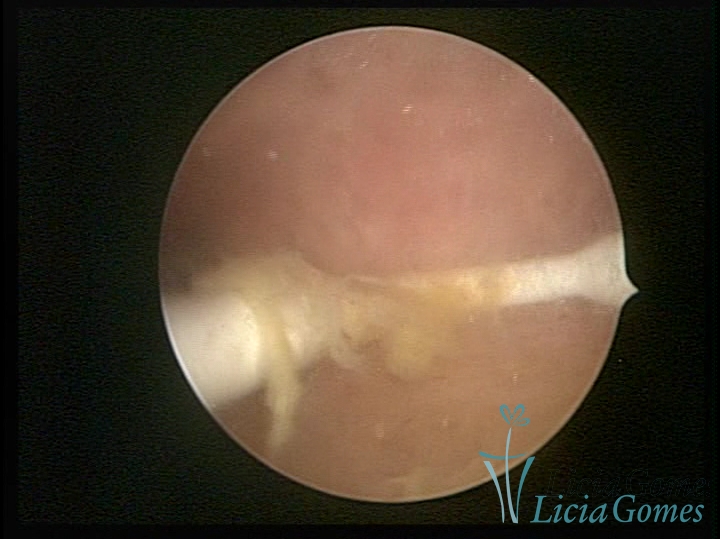

Cavidade uterina com DIU